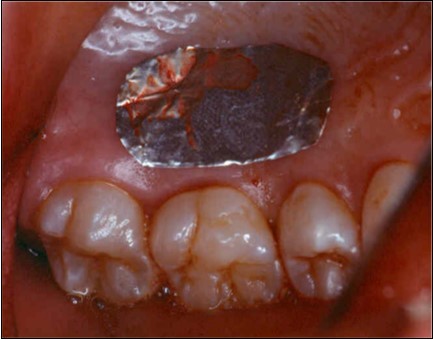

Donor Site

A second surgical site is created on the palate. The length of this is determined by the combines width of the teeth to be covered. The incisions are made in an anterior posterior direction. They are carried to the depth of the palatal mucosa, where they converge just short of the bone. A wedge of tissue is removed as free gingival graft, and its band of epithelium is excised by using Er:YAG laser and acute dissection with scalpel and blade 15C (Figure 4, Figure 4A). The graft is placed in the previously recipient site so that it completely covers the formerly exposed root area (Figure 5). It is then firmly sutured in place with 5-0 gut. The partial thickness, flap is positioned coronally in a manner to cover as much of the graft as possible and sutured in this position to promote maximum adaptation to ensure better healing with less chance of wound dehiscence (Figure 6). The donor site and recipient site is covered with surgical dressing and the patient is instructed in normal postsurgical management. The patient is seen on the 7th postoperative day to remove the surgical dressing and sutures. No additional dressing is necessary, and normal plaque control techniques are resumed (Figure 7)

Figure 4.Donor site area in the palate

Donor site area in the palate

Figure 4a.Elimination of the epithelium from free gingival graft by acute dissection

Elimination of the epithelium from free gingival graft by acute dissection